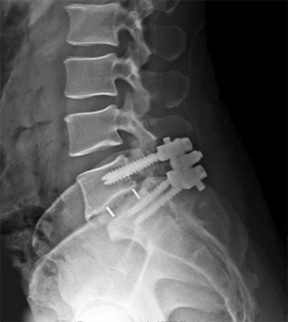

A 15-year-old female gymnast complains of chronic lower back pain and tightness in her hamstrings. Imaging reveals a Meyerding Grade II isthmic spondylolisthesis at L5-S1. Despite 6 months of dedicated physical therapy, bracing, and activity modification, her symptoms severely limit her daily activities. What is the most appropriate surgical intervention?